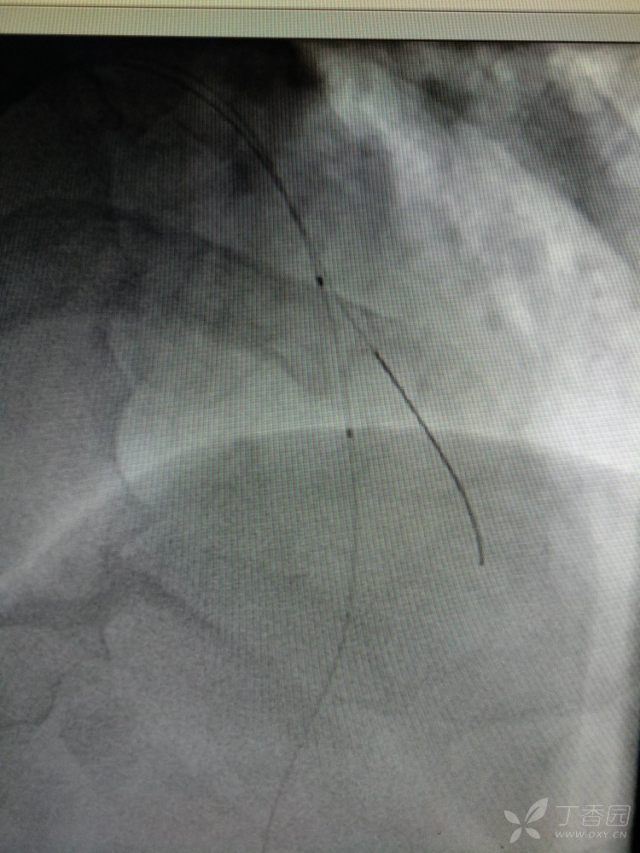

下面这些是急性心肌梗死的患者的心电图和造影的对比图,看见这些心电图要及时作出诊断。